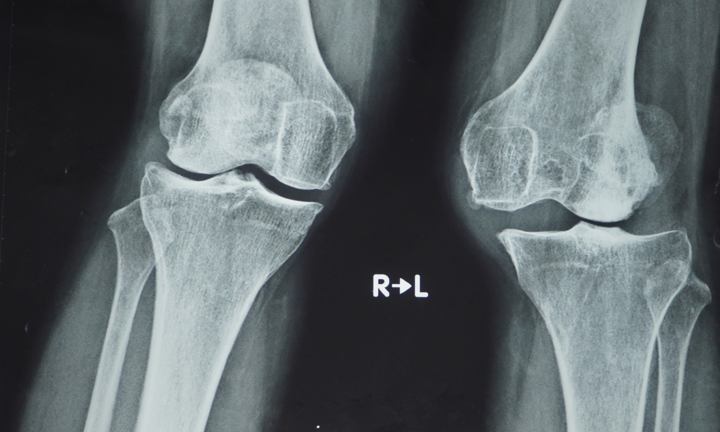

Lần đầu tại Việt Nam phẫu thuật thay khớp gối dạng bản lề bằng titanium

Một bệnh nhân nữ được thay khớp gối thì đầu bằng titanium, dạng bản lề lần đầu tiên được áp dụng thành công tại Việt Nam.